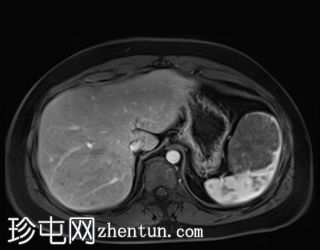

冠状位

T2加权像

T1低信号,T2低信号为主的脾脏肿块,内部可见T2高信号分隔,呈进行性强化。肿块中央可见星状瘢痕。

脾脏硬化性血管瘤样结节性转化(SANT),9.8 cm肿块

顾名思义,脾脏硬化性血管瘤样结节性转化(SANT)是一种纤维性血管病变。本病例展示了SANT的一些典型影像学特征,包括边界清晰的病灶,中央可见瘢痕,以及呈放射状进行性强化。这些特征使得术前MRI诊断较为明确。尽管SANT是一种良性病变,但大多数患者仍需行脾切除术以明确病理诊断。